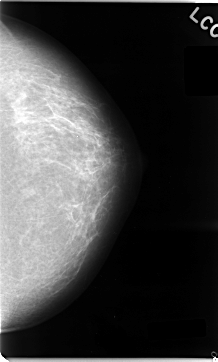

C_0035_1.LEFT_CC

LEFT_CC LINES 4696 PIXELS_PER_LINE 2824 BITS_PER_PIXEL 12 RESOLUTION 50 NON_OVERLAY